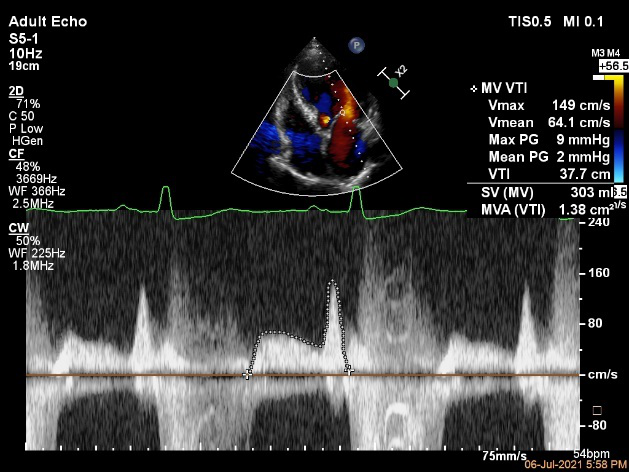

二尖瓣口平均跨瓣压差:1mmHg

夹子放置后二尖瓣口平均跨瓣压差:3mmHg

肺静脉血流频谱恢复正常